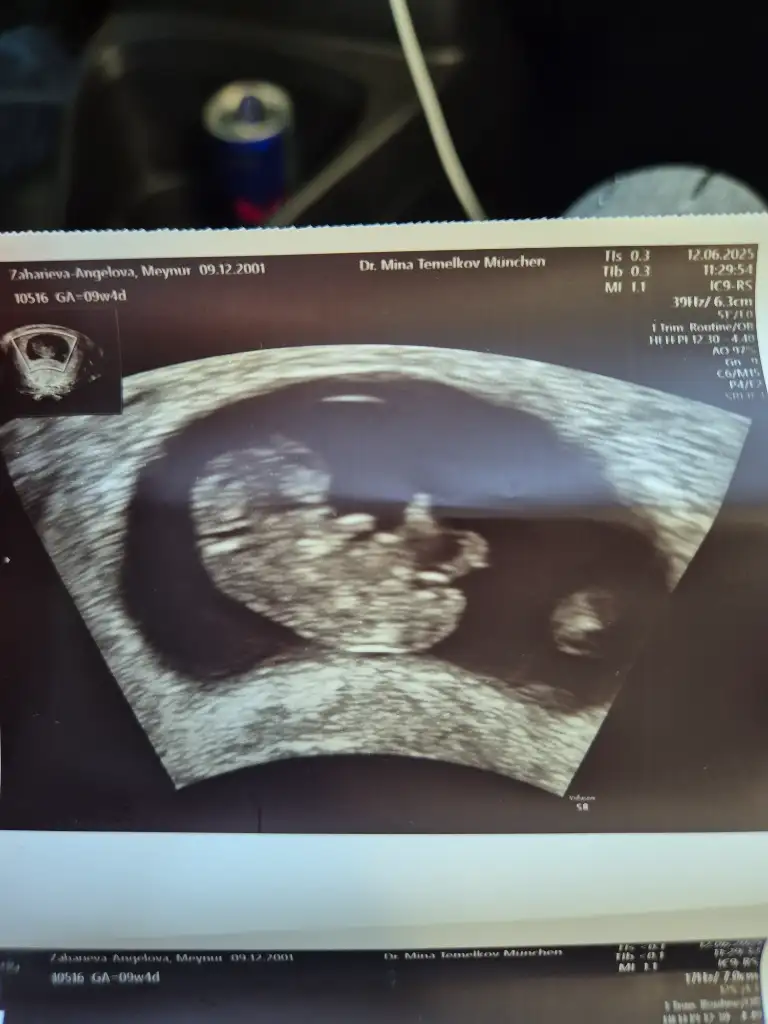

Kızlar 9haftalık gebelik sizce cinsiyet nedir?

Eklentiler

• 1000010842.webp

1000010842.webp

32,2 KB · Görüntüleme: 172

• 1000010843.webp

1000010843.webp

29,2 KB · Görüntüleme: 155